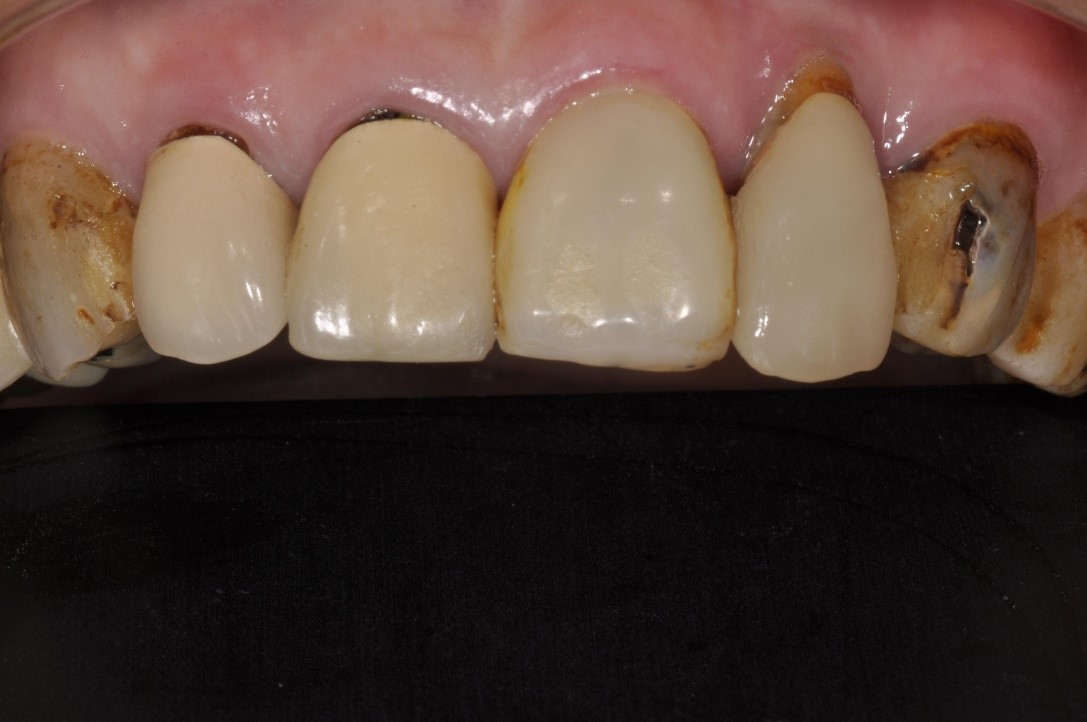

前牙修復及立即植牙-蛀牙-#13-23

人工植牙

前牙美學

立即植牙-前牙